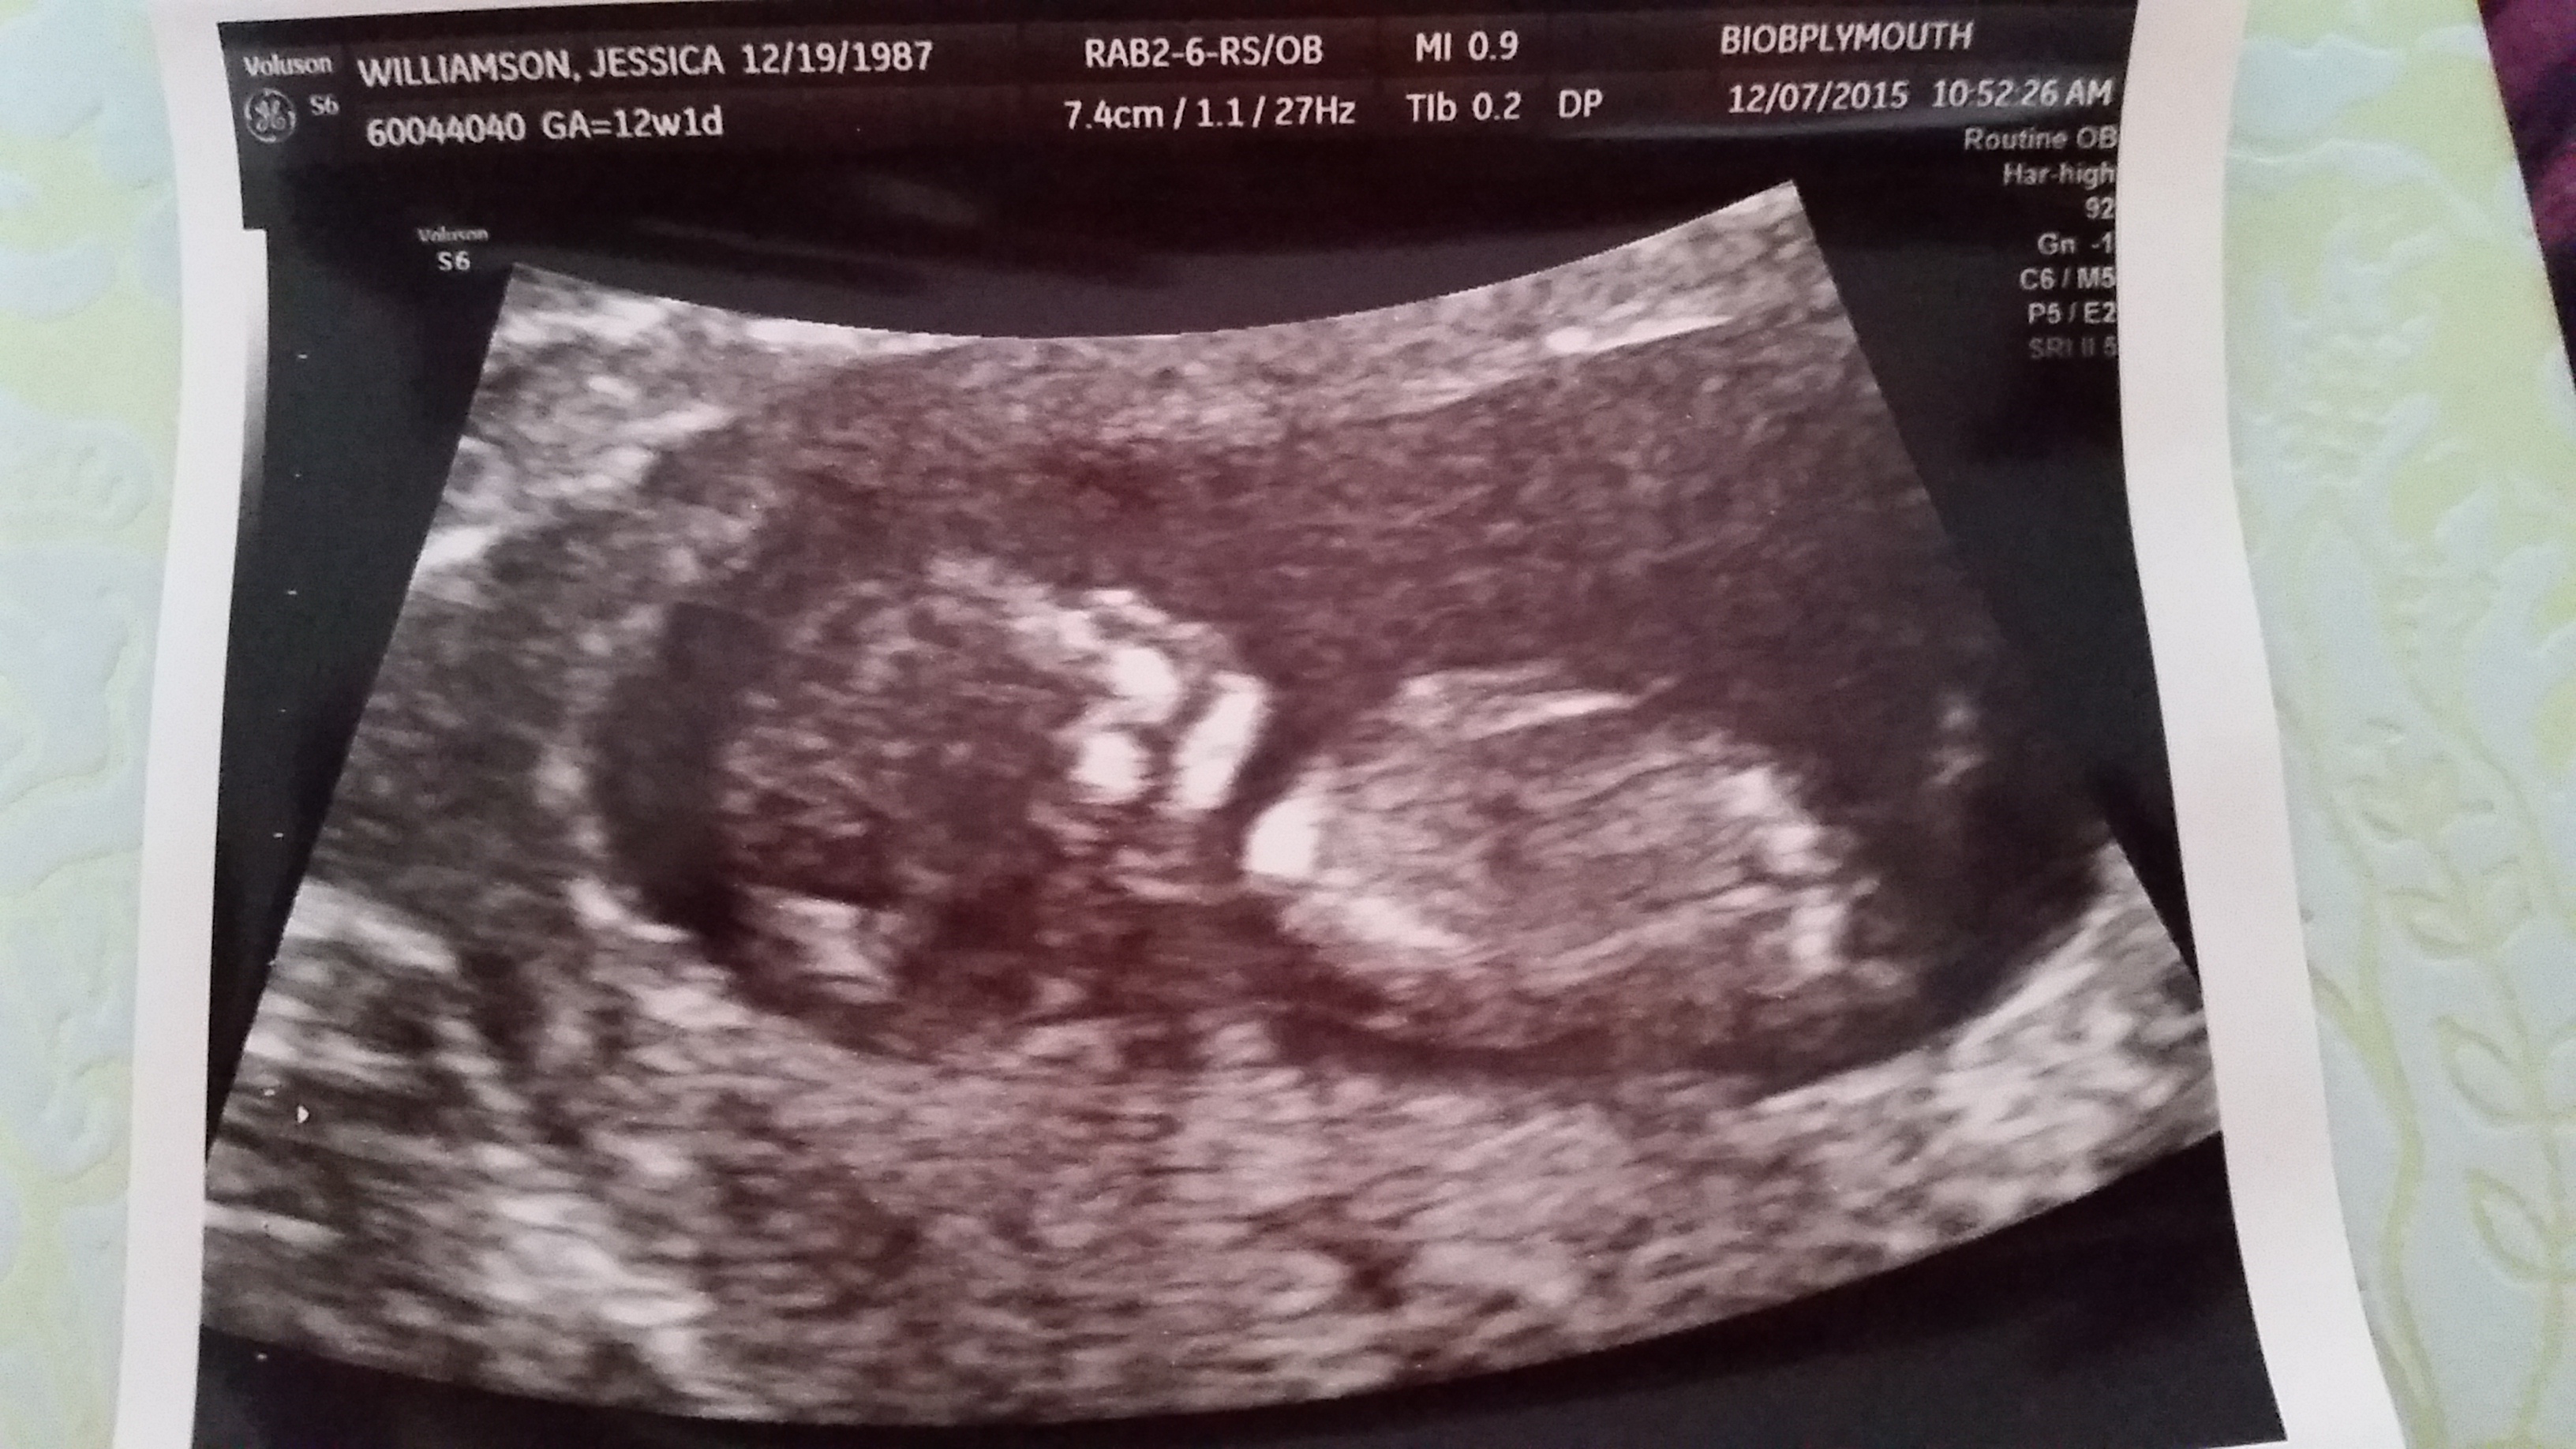

Had my NT scan today. Such a huge difference from my 7 week ultrasound. It actually had arms and legs this time!!

12w 1d

I ask because you have a textbook nub and didn't want to tell you if you if you didn't want to know lol it's basically one of the only theories that are pretty accurate. (I hope I don't get flamed)

I have actually been thinking about this but I have no clue if it's nub or leg (maybe even cord). We didn't notice it while we were in the scan, only after we got home. I told my husband about it because he's been convinced it's a boy since we got pregnant (his main reasoning was that since HE is a boy, baby will be a boy) :)

I don't think you'll get flamed, at least not from me. I have some OB/GYN friends who actually told us about this method a few weeks ago, so I'd say it's pretty valid. It totally slipped our minds once we were at the appointment. I may have to run this picture by them.

I did a ton of research on this when I was pregnant with my son and I would be absolutely amazed if it wasn't a boy with how clear that image is. I'm curious to see what your friends say, keep me updated!